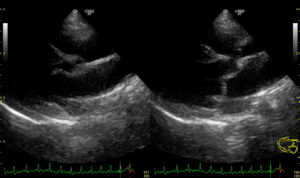

エコー(超音波)検査

エコー検査では様々な評価を行います。

雑音が聴こえる原因を探したり、重症度を評価したりします。

エコー検査はおよそ15分~30分で完了します。初めての検査の際は時間がかかる事もあるため、お昼の時間にお預かりして検査させていただきます。検査には特に麻酔などは必要ありません。

僧帽弁閉鎖不全症の治療開始の目安となるACVIMのステージ分類(A~Dまで)はレントゲン検査とエコー検査を組み合わせて評価します。

現在は、Stage B-2から治療を開始することが一般的となっています。